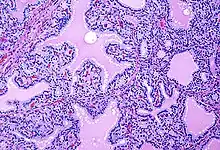

Biopsy to obtain histiological testing is not normally required, but may be obtained if thyroidectomy is performed.